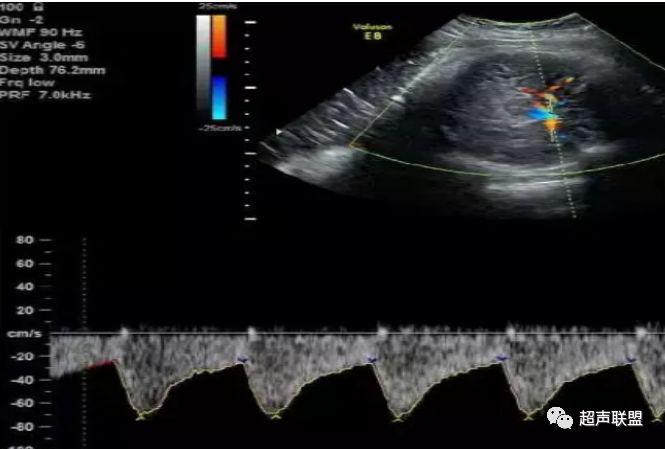

4 脐静脉频谱

胎儿宫内缺氧严重时脐静脉出现搏动。

6、脐静脉:脐静脉搏动(见于严重的胎儿宫内缺氧);

4、脐静脉搏动。

图9 脐静脉搏动